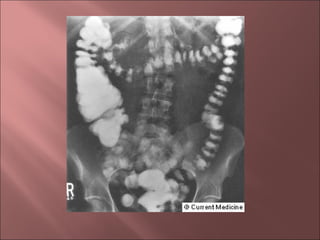

   Estudios con bario.

   Colonoscopia.

•Enema baritado y colonoscopia: contraindicados en fase aguda

•Enema hidrosoluble

•Rx Simple                         Diagnóstico

•Tórax: Perforación

•Abdomen

•Dilatación de ID y de IG

•Obstrucción intestinal

•Opacidades de partes blandas: abscesos